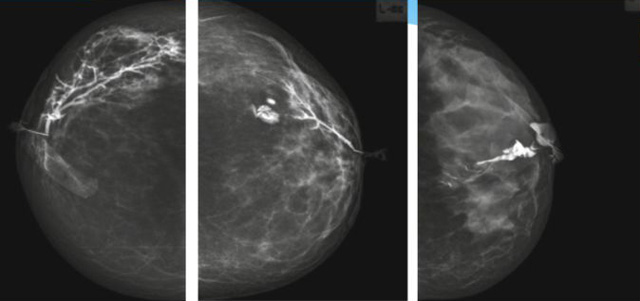

乳腺導(dǎo)管內(nèi)乳頭狀瘤分為以下兩個,位于乳暈區(qū)大導(dǎo)管的中央型乳頭狀瘤,起源于末梢導(dǎo)管小葉單位的外周型乳頭狀瘤。外周型乳頭狀瘤常常沒有明顯的的臨床表現(xiàn),常因X線或乳腺超聲設(shè)備檢查發(fā)現(xiàn)。重點要關(guān)注的是中央型乳頭狀瘤,發(fā)生于任何年齡的女性,以40~50歲者居多。它表現(xiàn)為:單側(cè)乳頭溢液,特別是血性溢液少數(shù)病人可在乳暈區(qū)觸及腫塊。從病理學(xué)上面講表現(xiàn)為導(dǎo)管上皮和間質(zhì)增生形成有纖維脈管束的乳頭狀結(jié)構(gòu)。這是它一個病理學(xué)上的表現(xiàn)。它的超聲表現(xiàn)為:病變導(dǎo)管囊狀擴(kuò)張呈無回聲,內(nèi)可見乳頭狀低回聲或中等回聲。乳暈處的導(dǎo)管擴(kuò)張,管腔內(nèi)可見邊界清楚的,低回聲實性結(jié)節(jié)。外周型導(dǎo)管內(nèi)乳頭狀瘤可,表現(xiàn)擴(kuò)張為為低回聲的實性結(jié)節(jié),CDFI:部分腫瘤可顯示為軸心性的看到血流信號。乳腺增生癥:可見導(dǎo)管擴(kuò)張,內(nèi)無乳頭狀實性回聲,導(dǎo)管內(nèi)乳頭狀癌:囊內(nèi)乳頭狀癌病變較大,不規(guī)則,厚基底,血流豐富。以囊性為主的混合回聲,形態(tài)不規(guī)則,內(nèi)見實性低回聲實性低回聲可見少量血流,病理為囊內(nèi)乳頭狀癌。

乳腺超聲設(shè)備檢查的價值在哪里呢?它可以檢查發(fā)現(xiàn)乳暈周圍的各種病變,對于單側(cè)乳頭溢液、血性溢液的患者,超聲是首選的影像學(xué)檢查方法。注意:導(dǎo)管內(nèi)乳頭狀瘤可合并不典型增生或,導(dǎo)管內(nèi)乳頭狀癌,手術(shù)前懷疑時候,就應(yīng)該手術(shù)切除而不是用微創(chuàng)手術(shù)。